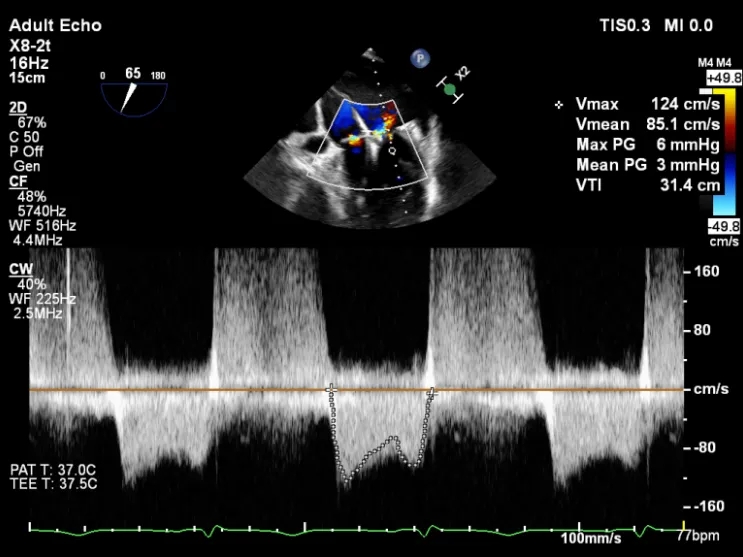

第二枚XTR植入后瓣口平均压差3mmHg

第3枚XTR夹合器植入后,跨瓣平均压差为3mmHg

肺静脉收缩期逆流消失,频谱形态基本恢复正常